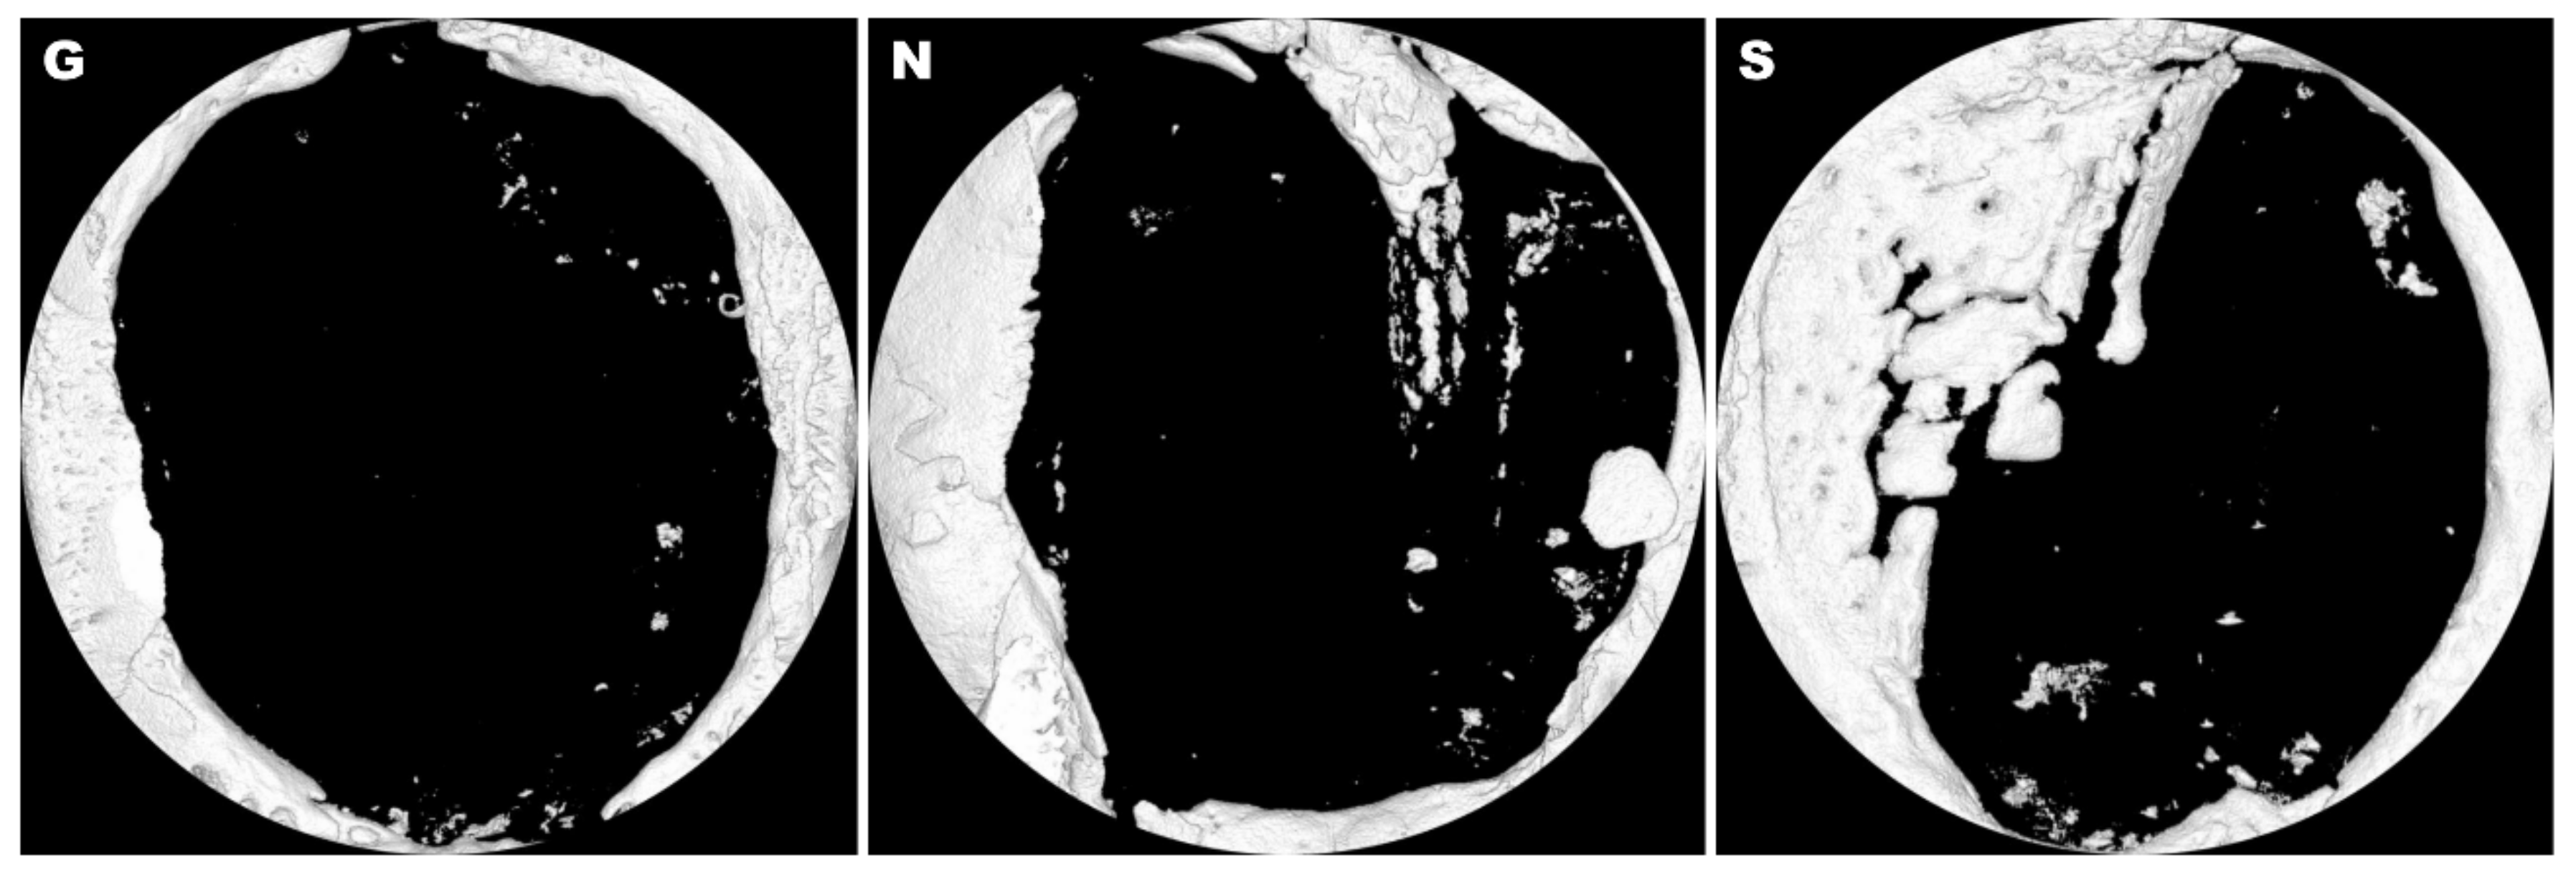

3.1. MicroCT Analysis

| Bone volume (mm3) | 1.24 ± 1.05 | 1.71 ± 1.65 | 3.87 ± 2.51 * |